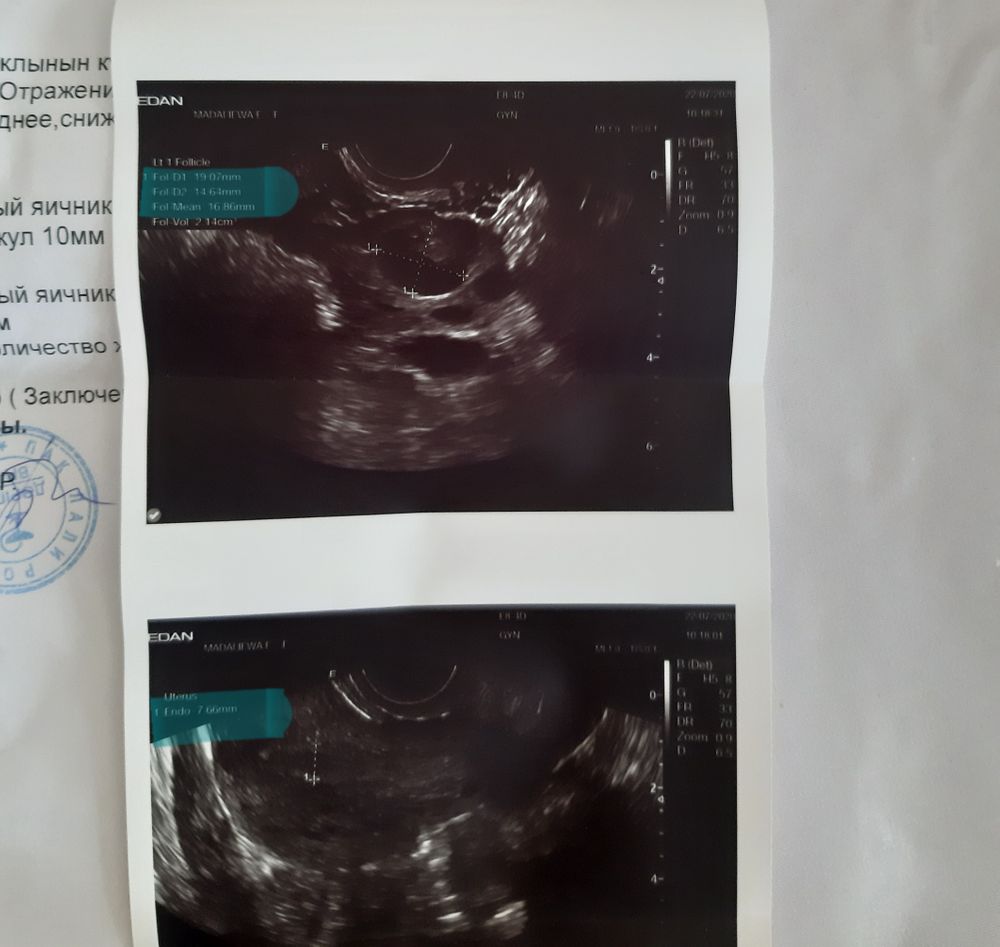

ФолликулометрияДд! Ничего не пойму, сегодня на 13 д.ц по УЗИ, со слов гинеколога овуляция была совсем недавно, видно желтое тело и жидкость. В другом яичнике дф 10 мм. Эндометрий 7,6 мм. Но на снимке совсем другие данные: дф1: 19,07 мм, дф2 14,64 мм, главный фолл 16,88 мм (не знаю что это за показатель), а эндометрий соответствует снимку: 7,6 мм.

Посмотрите пожалуйста снимок, я там выделила.

Получается, у меня еще не было овуляции, раз дф 19 мм? Или на снимок можно не смотреть? Но врач по монитору мне показывала и говорила, вот желтое тело и вот жидкость. Теперь уже совсем запуталась. Тест на овуляцию слабо-положительный. И до этого с мая у меня не было овуляции, в прошлом был дф 17,6мм, но он не лопнул даже при уколе ХГЧ 3000 ед. И цикл был длинный 32 дня. А овуляция на 12 или 13 д.ц очень удивительно. И ещё я не знаю, жить ли мне половой жизнью теперь или нет. ПА у нас был вчера ночью, есть ли смысл сегодня жить?